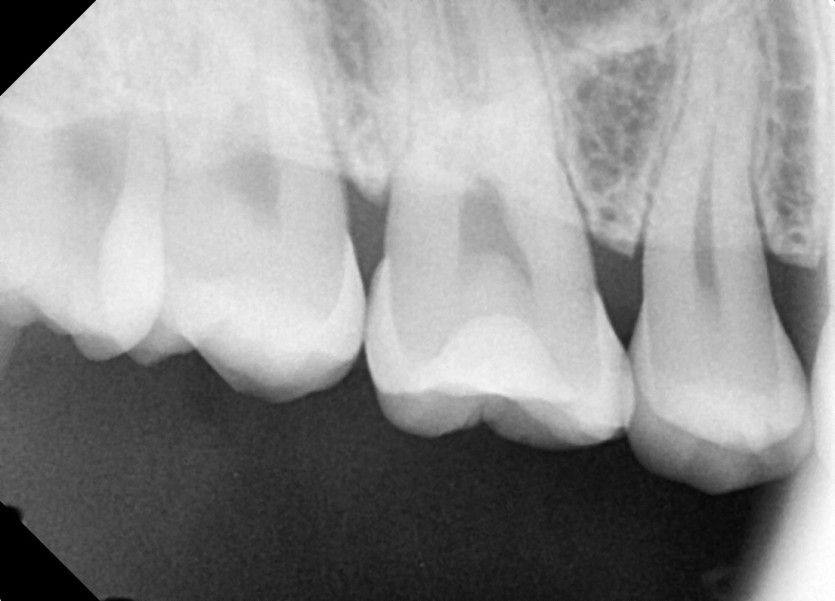

#18,48 사랑니 발치

구강외과 전문의가 당일발치 했습니다.